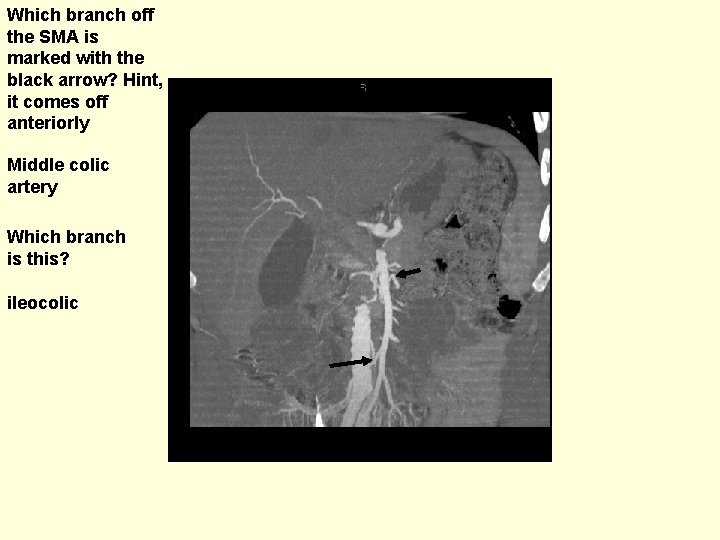

Which branch off the SMA is marked with the black arrow? Hint, it comes off anteriorly Middle colic artery Which branch is this? ileocolic

Which branch is this? (kind of subtle in this patient) Right colic artery Which vessel is this coming off the aorta? IMA